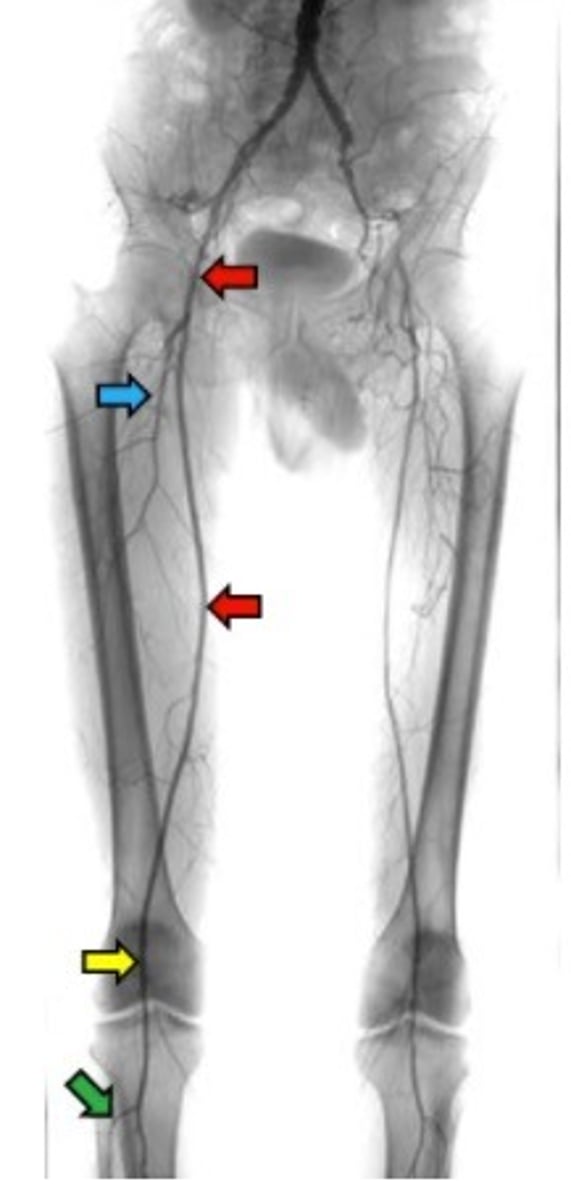

great saphenous vein

Which vein is the longest vein in the body?

Right femoral artery

anterior tibial artery